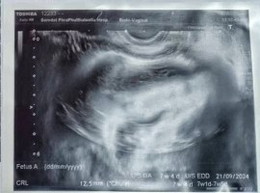

ผลอัลตร้าซาวด์ผ่านช่องคลอด

เเม่ๆช่วยดูให้หน่อยได้มั้ยคะ ว่าตรงไหนคือน้อง เเม่มองไม่ออกเลย เเต่หมอเเจ้งเเล้วว่า พบหัวใจน้องเเล้ว อยู่ในมดลูกค่ะ อายุครรภ์ตามใบซาวด์ช้ากว่า การนับประจำเดือน 1สัปดาห์ค่ะ

รอบหน้าถ้าสงสัยให้ถามหมอเลยค่ะ เพราะถ้าซาวด์ 2 มิติตอนน้องยังเล็กจะเป็นก้อนๆแล้วมีหัวใจกระพริบๆ ต้องดูภาพเคลื่อนไหวที่จอ